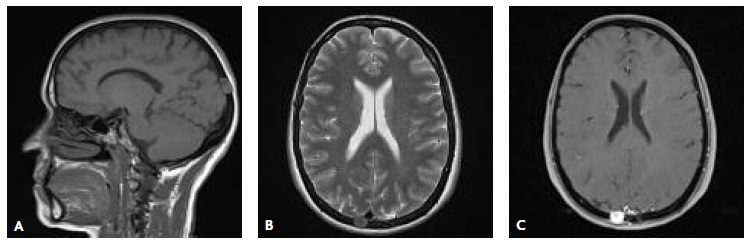

Na consulta de neurocirurgia a avaliação foi complementada com a realização de ressonância magnética crânio-encefálica (RM-CE), que confirmou a presença de uma pequena lesão ocupando espaço, centrada ao diploé, com topografia occipital superior para-sagital direita, de configuração ovalada e com cerca de 15mm de maior diâmetro. Apresentava contornos regulares e limites bem definidos, sem integridade da tábua interna e externa, com discretos componentes epicraniano e extra-axial intracraniano, e aparente base de implantação dural, mas sem dural tail. Após administração de gadolínio documentou-se um reforço homogéneo e intenso de sinal. Confirmou-se o contacto com o seio longitudinal superior, sem moldagem ou desvio do mesmo, encontrando-se o seu calibre e a sua permeabilidade mantidas (Figura 3).

Figura 3 RM-CE mostrando a lesão na topografia occipital superior para-sagital direita, nos planos sagital (A), axial (B) e após administração de gadolínio (C).

Na RM-CE, as imagens ponderadas em T1 mostram lesões isointensas ou hipointensas em comparação com a substância cinzenta, enquanto as ponderadas em T2 são variáveis, mas geralmente hiperintensas; no entanto, a hipointensidade não exclui o diagnóstico de meningioma.1 Um realce homogéneo intenso, após a administração de gadolínio, é visto tipicamente. Normalmente as lesões não apresentam dural tail, que corresponde a um espessamento dural marginal típico.1 Quando este é visualizado, pode ser secundária a invasão dural ou irritação provocada pelo tumor.

No caso descrito, a doente tinha 58 anos e não apresentava história de trauma significativo ou fratura craniana antiga. Não se verificou a presença de alterações neurológicas atribuídas à lesão; contudo, ficou patente a inespecificidade dos sintomas que pode estar presente numa fase inicial. Apresentava os rastreios oncológicos atualizados, de acordo com a faixa etária e com resultados normais. A investigação laboratorial não revelou alterações. Na radiografia, a lesão apresentou-se como uma imagem de morfologia arredondada e hipertransparente, traduzindo a sua natureza osteolítica. A TC-CE confirmou a lesão lítica na calote craniana, associada a erosões completas da tábua interna e externa do crânio e do espaço diploico. Na RM-CE, a lesão exibia discreto componente epicraniano, pequeno extra-axial intracraniano e aparente base de implantação dural, mas sem dural tail. A doente foi submetida a craniotomia para exérese do tumor e cranioplastia com material sintético. O pós-operatório decorreu sem intercorrências. A doente mantém seguimento em neurocirurgia, onde fará reavaliação imagiológica posterior no sentido de confirmar a ausência de recidiva.